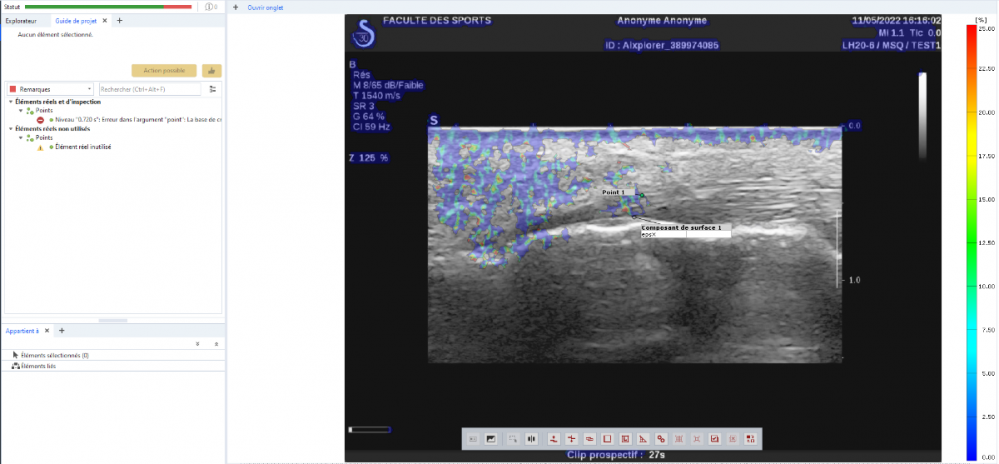

[Zo...] Posted June 17, 2022 Author Share Posted June 17, 2022 Here is a screenshot of the error I get at the end of the calculation. Link to comment Share on other sites More sharing options...

[Iv...] Posted June 20, 2022 Share Posted June 20, 2022 It seems that the SW can't create/find the point component anymore. Do you have any greater movement in between two stages of your point component? Do you have a rigid or deforming component? Can you make two screenshots? One in a stage were the component is found and one with the error? Check also in the creation parameter of your component (click F4, while the component is selected) and tell me the component type Link to comment Share on other sites More sharing options...

[Zo...] Posted June 20, 2022 Author Share Posted June 20, 2022 This is an ultrasound video of a tendon at the point where it hooks onto the bone. My goal is to get the deformations at the interface tendon/bone. It is a deformable component which evolves in a deformable environment since the whole of the video (fat, bone) moves because of the movement. The component type is surface component (calculation option : get more points) as it is a 2D video. Link to comment Share on other sites More sharing options...

[Zo...] Posted June 20, 2022 Author Share Posted June 20, 2022 I made here the calculation on the whole video because by selecting only the part of interest the calculation does not work at all Link to comment Share on other sites More sharing options...

[Iv...] Posted June 21, 2022 Share Posted June 21, 2022 Thanks Zoe, the screenshots are very helpful. The main problem is that your surface is not as good as it should be for a deformation analysis. Especially the grayvalue distribution. The point you created is based on the surface component. If you lose your surface component you lose your point. This is the error you see in your screenshot. If would recommend, if you like to inspect a discrete point, to create a facet point. There you use a facet to create and find a specific point. Link to comment Share on other sites More sharing options...